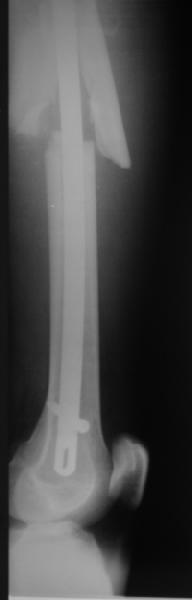

Уважаемые коллеги! От имени Алексея Смирнова всем спасибо за обсуждение. Больной прооперирован. Снимки в приложении.

При наличии различных имплантов, любые варианты: слева (полу) открытым - мининвазивным, а справа закрытым интрамедуллярным методом, его считаем более чем приемлемым для фиксации данных переломов.

Проксимальная и дистальная блокировка, независимо от техники введения штифта, ретроградно или антеградно, гарантирует сращение сегментарных переломов бедра без укорочения. Штифты диаметром 12 мм с блокировкой сверху и вниз двумя шурупами выдерживают вес 75 кг больного, что позволяет раннюю профилактику контрактур.